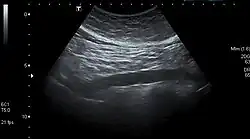

Abdominal aorta ultrasound Abdominal aorta ultrasound